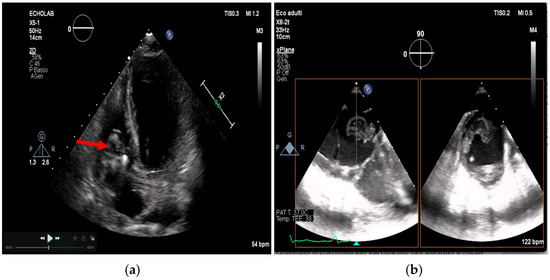

Multimodality Imaging in Infective Endocarditis: A Clinical Approach to Diagnosis

by Leonardo Brugiatelli, Francesca Patani, Carla Lofiego, Martina Benedetti, Irene Capodaglio, Pongetti Giulia, Francioni Matteo, Paolini Enrico, Nazziconi Marco, Kevin Maurizi, Furlani Giulia, Massari Arianna, Luciani Simone, Anselmi Benedetta, Gatti Chiara, Schicchi Nicolò, Fogante Marco, Tarsi Giovanni, Dello Russo Antonio, Di Eusanio Marco, Marini Marco and Fabio Vagnarelliadd Show full author list remove Hide full author list

Medicina 2025, 61(12), 2241; https://doi.org/10.3390/medicina61122241 - 18 Dec 2025

Infective endocarditis (IE) is a life-threatening condition with a rising incidence, demanding rapid and precise diagnosis. While echocardiography remains the cornerstone of initial evaluation, its limitations in complex cases—such as those involving prosthetic valves or cardiac devices—are well-known. This review synthesizes current evidence [...] Read more.

Infective endocarditis (IE) is a life-threatening condition with a rising incidence, demanding rapid and precise diagnosis. While echocardiography remains the cornerstone of initial evaluation, its limitations in complex cases—such as those involving prosthetic valves or cardiac devices—are well-known. This review synthesizes current evidence and guidelines to outline a practical, multimodality imaging approach for IE. We emphasize that integrating advanced techniques like cardiac computed tomography (CT) and [18F]-fluorodeoxyglucose positron emission tomography/computed tomography (FDG PET/CT) early in the diagnostic pathway, particularly in high-risk scenarios, significantly enhances diagnostic certainty, guides therapeutic decisions, and improves patient outcomes. A tailored imaging strategy, driven by clinical presentation and integrated within a multidisciplinary endocarditis team, is paramount for modern IE management. Full article

(This article belongs to the Special Issue Diagnosis and Treatment of Valvular Heart Diseases)

Show Figures

Figure 1